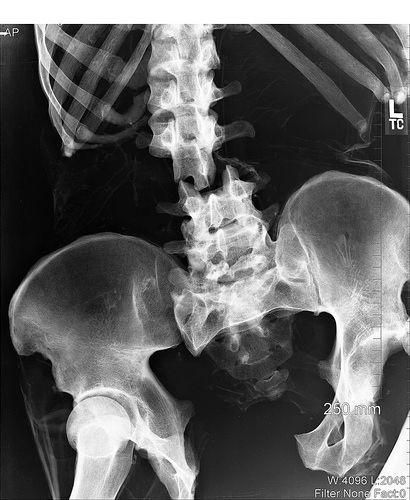

Результат падения с высоты. Перелом позвоночника